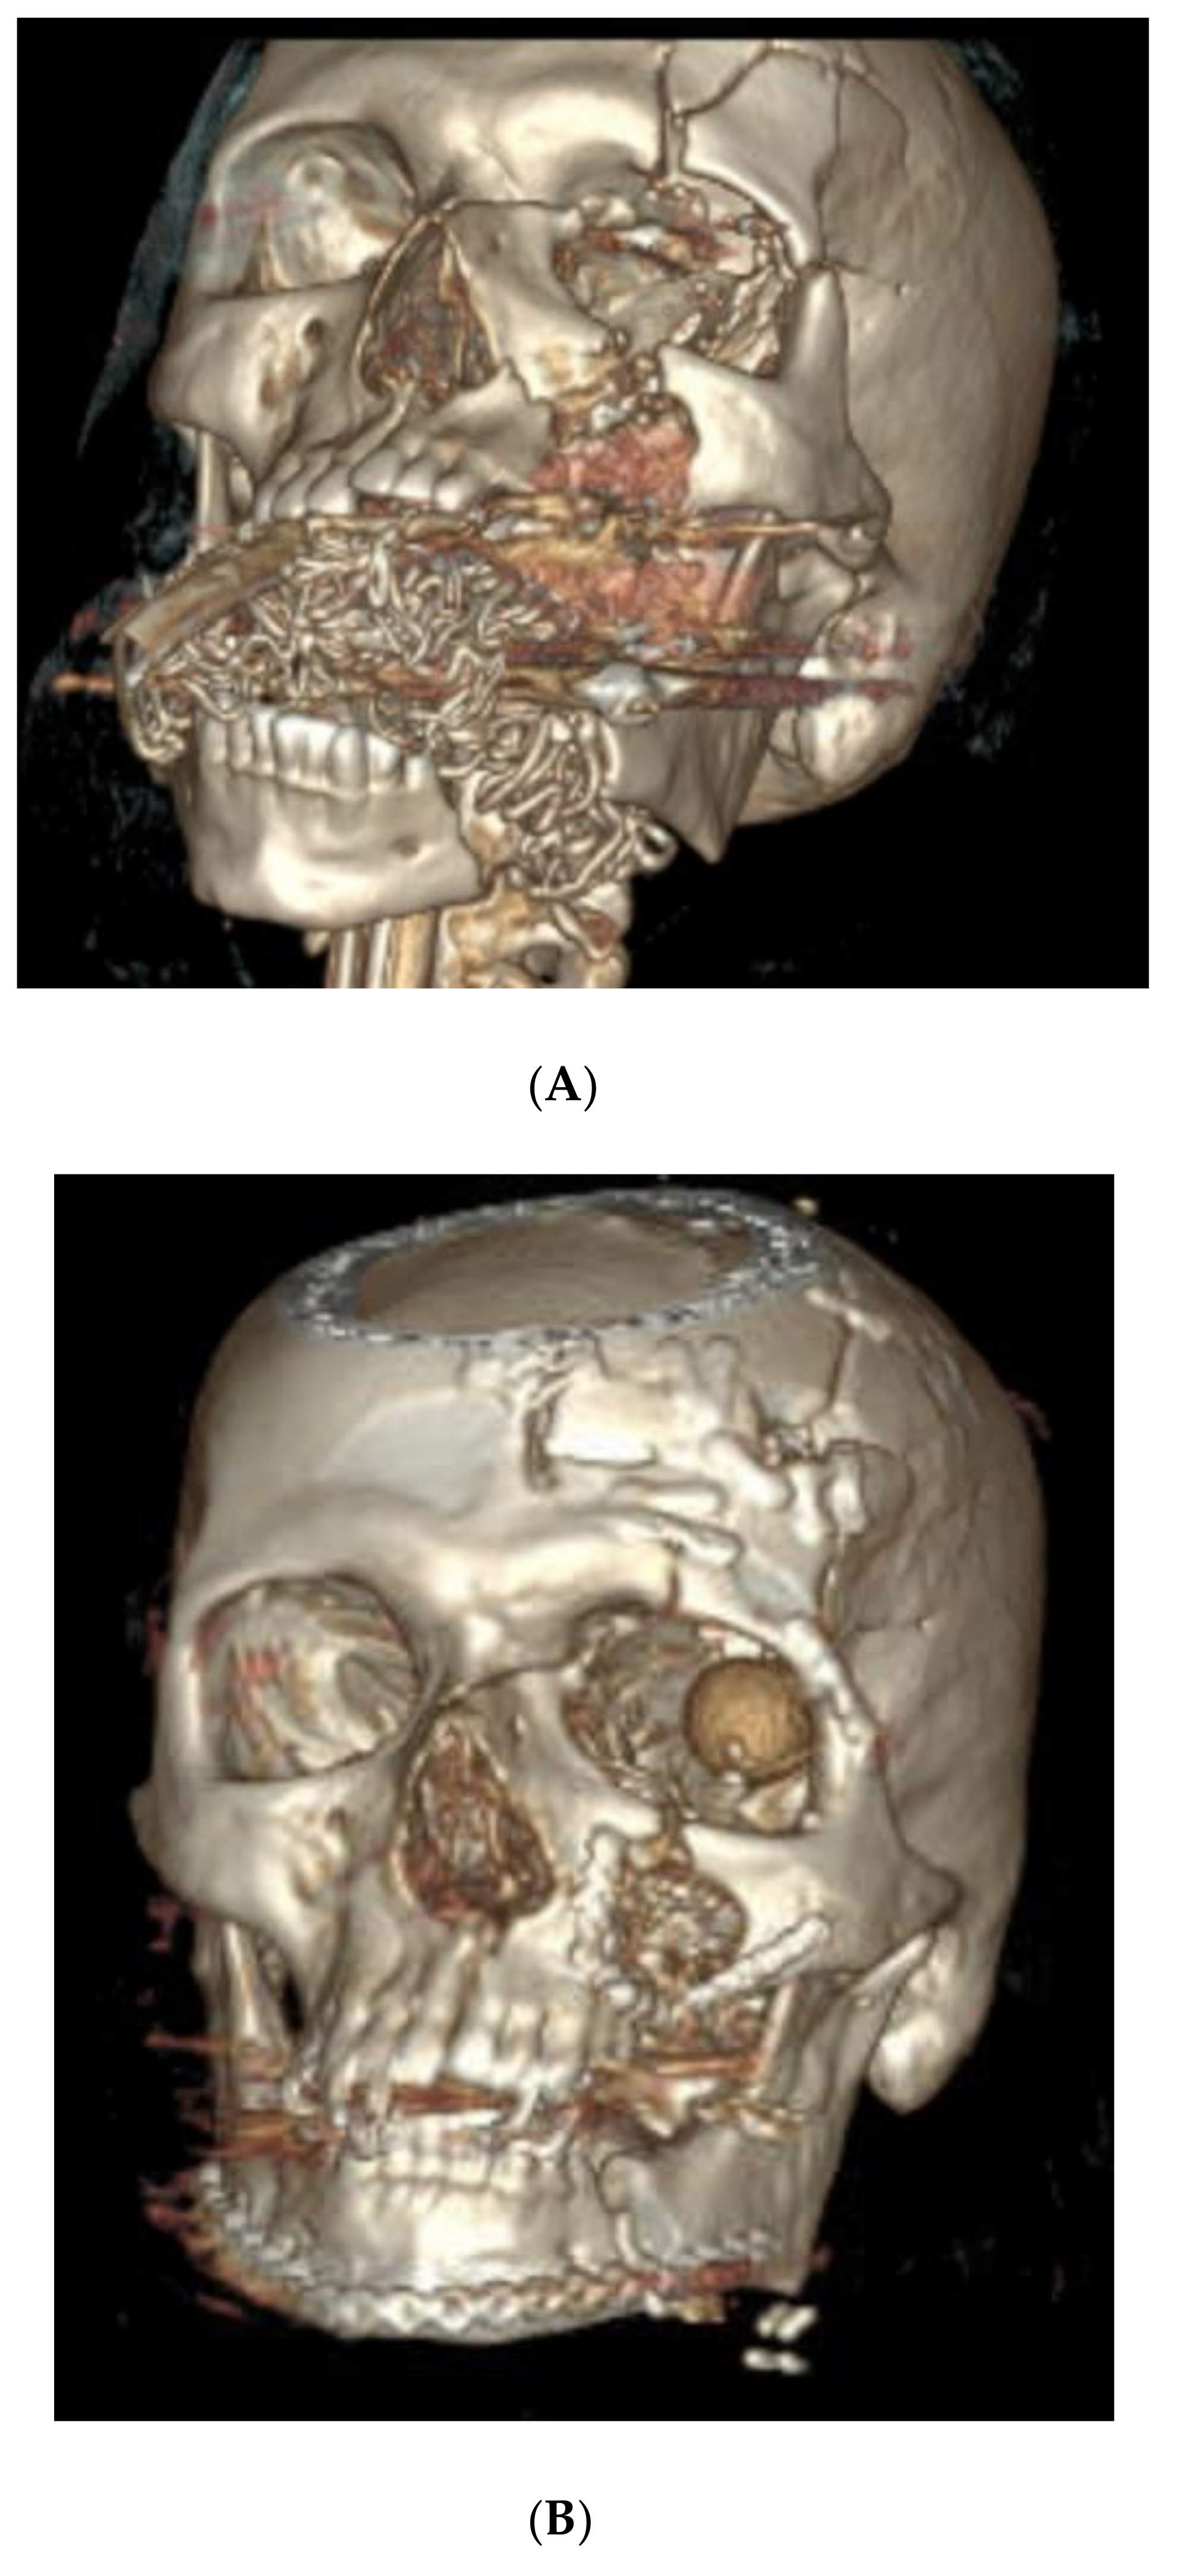

4.3. Case 3 (Patient 3D Model, Occlusal Splint, 3D Printed Plate)

- Left orbital floor and lateral orbital rim fractures;

- Comminuted maxillary fractures with involvement of the hard palate and retained bullet fragments in the maxillary sinus;

- An extensively comminuted open fracture of the left mandibular body extending to the parasymphysis;

- Extensive soft tissue and dental injuries with retained ballistic fragments.